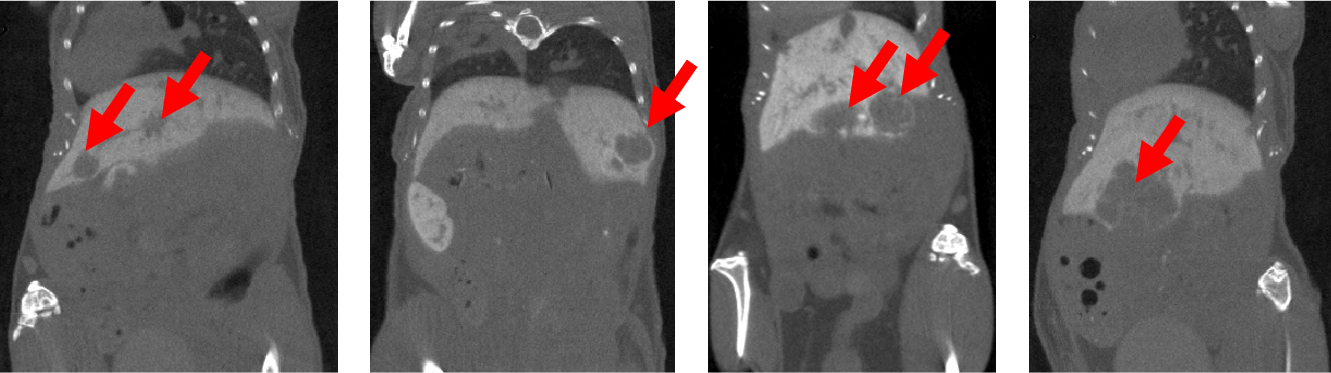

6、對(duì)比增強(qiáng)腫瘤CT成像

腫瘤研究:對(duì)比增強(qiáng)CT檢查活體小鼠肝腫瘤:注射顯影增強(qiáng)劑Exitron 12000,F(xiàn)DK重建,成像時(shí)間:4min,100μm voxel size。

腫瘤成像.png

7、新冠肺炎CT成像

檢測(cè)活體敘利亞倉(cāng)鼠的肺部CT影像:定性分析方法:根據(jù)CT影像進(jìn)行病變程度評(píng)分;定量分析方法:通過分析像素密度在56-255范圍內(nèi)的圖像部分,定量分析CT影像上的不含氣肺體積(肺組織體積)(non-aerated lung volume);通過分析像素密度在0-55范圍內(nèi)的圖像部分,定量分析氣管(airways)和含氣肺體積(aerated lung volume)。影像表明:黃色箭頭表示肺實(shí)變,藍(lán)色箭頭表示支氣管擴(kuò)張。

圖8. CT影像.png